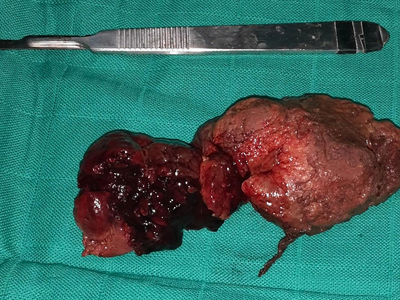

An “enormous” gossypiboma, which is a mass inside the body composed of retained surgical gauze or sponge surrounded by an inflammatory foreign body reaction.